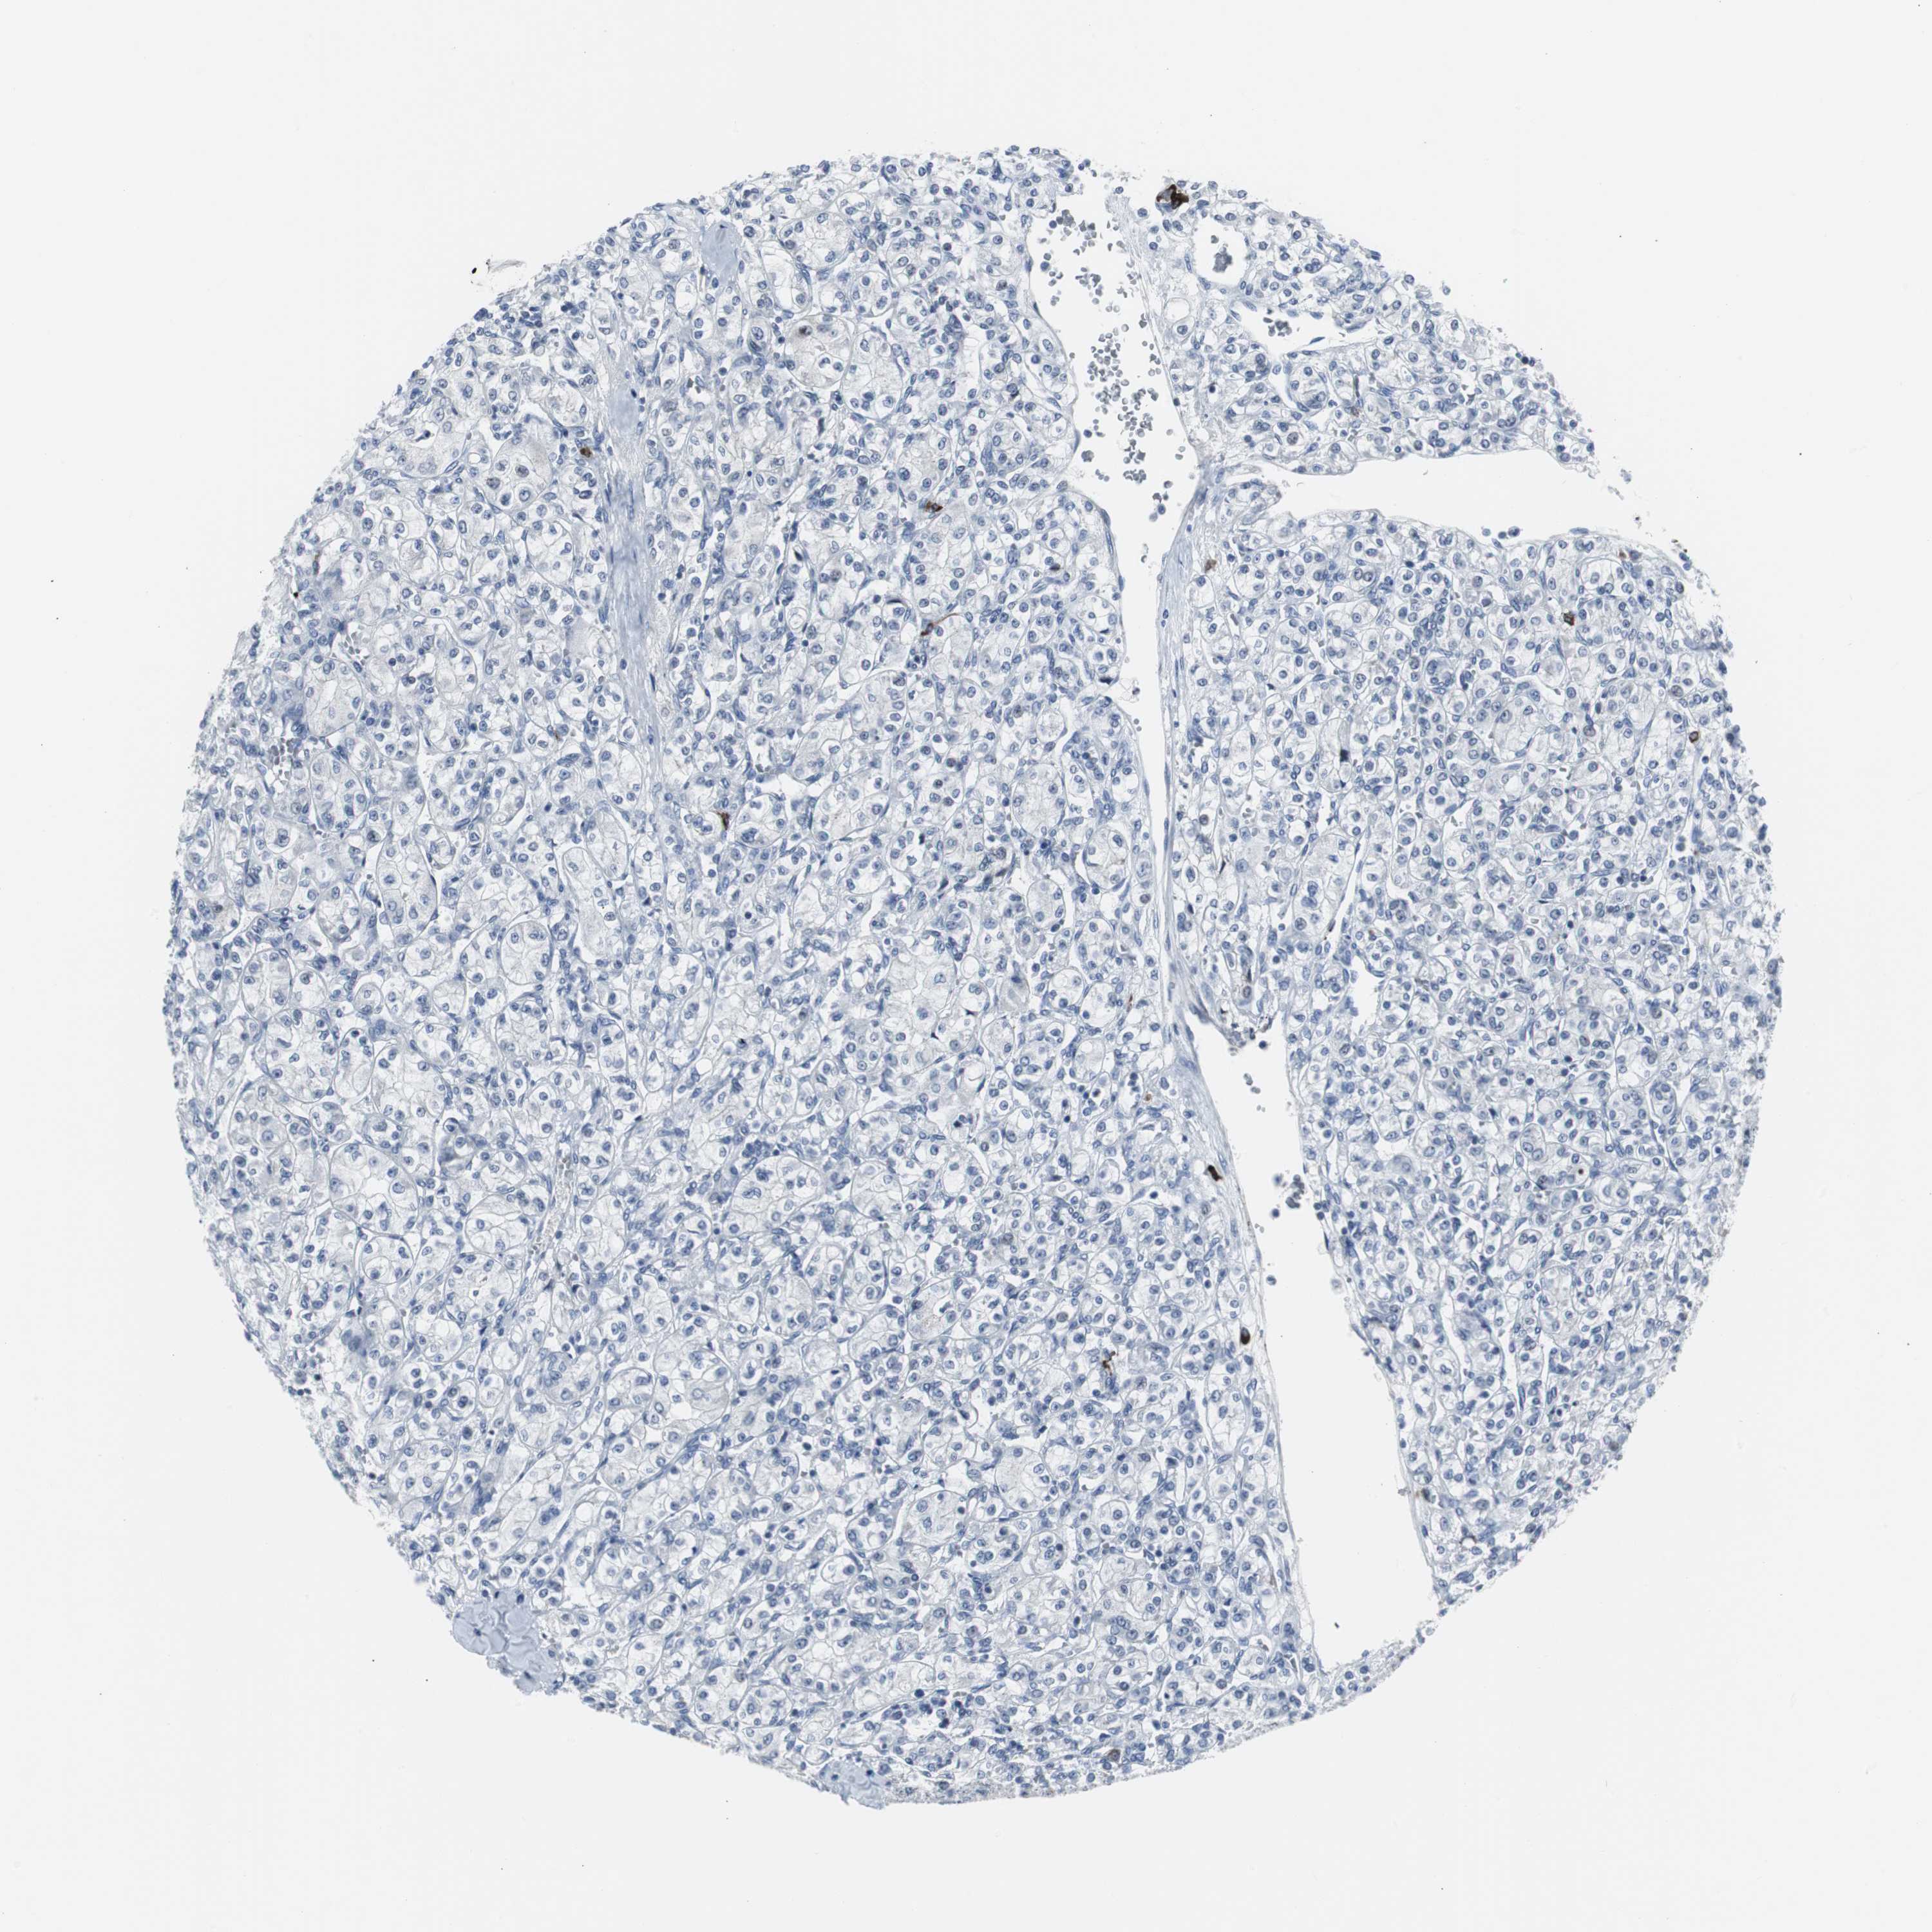

KIDNEY RENAL CLEAR CELL CARCINOMA (TCGA) - Interactive survival scatter ploti

The Survival Scatter plot shows the clinical status (i.e. dead or alive) for all individuals in the patient cohort, based on the same data that underlies the corresponding Kaplan-Meier plots. Patients that are alive at last time for follow-up are shown in blue and patients who have died during the study are shown in red.

The x-axis shows the expression levels (FPKM) of the investigated gene in the tumor tissue at the time of diagnosis. The y-axis shows the follow-up time after diagnosis (years). Both axes are complimented with kernel density curves demonstrating the data density over the axes. The top density plot shows the expression levels (FPKM) distribution among dead (red) and alive patients (blue). The right density plot shows the data density of the survived years of dead patients with high and low expression levels respectively, stratified using the cutoff indicated by the vertical dashed line through the Survival Scatter plot. This cutoff is automatically defined based on the FPKM cutoff that minimizes the p-score. The cutoff can be changed by dragging the vertical line or by entering a cutoff value in the square labeled "Current cut-off".

Under the Survival Scatter plot the p-score landscape (black curve; left axis) is shown together with dead median separation (red curve; right axis). Dead median separation is the difference in median mRNA expression between patients who have died with high and low expression, respectively. It is calculated as follows: median FPKM expression of dead patients with high expression - median FPKM expression of dead patients with low expression. This is intended to aid the user in visually exploring custom cutoffs and the associated p-scores and dead median separation.

Individual patient data is displayed and can be filtered by clicking on one or more of the category buttons on the top of the page. Categories describing expression level and patient information include: high, low, alive, dead, female, male and tumor stages. The scale of the x-axis can be toggled between linear and log-scale by clicking on the "x log" button. Mouse-over function shows TCGA ID, patient information and mRNA expression (FPKM) for each patient.

& Survival analysisi

Kaplan-Meier plots summarize results from analysis of correlation between mRNA expression level and patient survival. Patients were divided based on level of expression into one of the two groups "low" (under cut off) or "high" (over cut off). X-axis shows time for survival (years) and y-axis shows the probability of survival, where 1.0 corresponds to 100 percent.

DOK1 is not prognostic in Kidney Renal Clear Cell Carcinoma (TCGA)

Best expression cut offi

: 6.68

Average pTPM 8.8

Number of samples 521